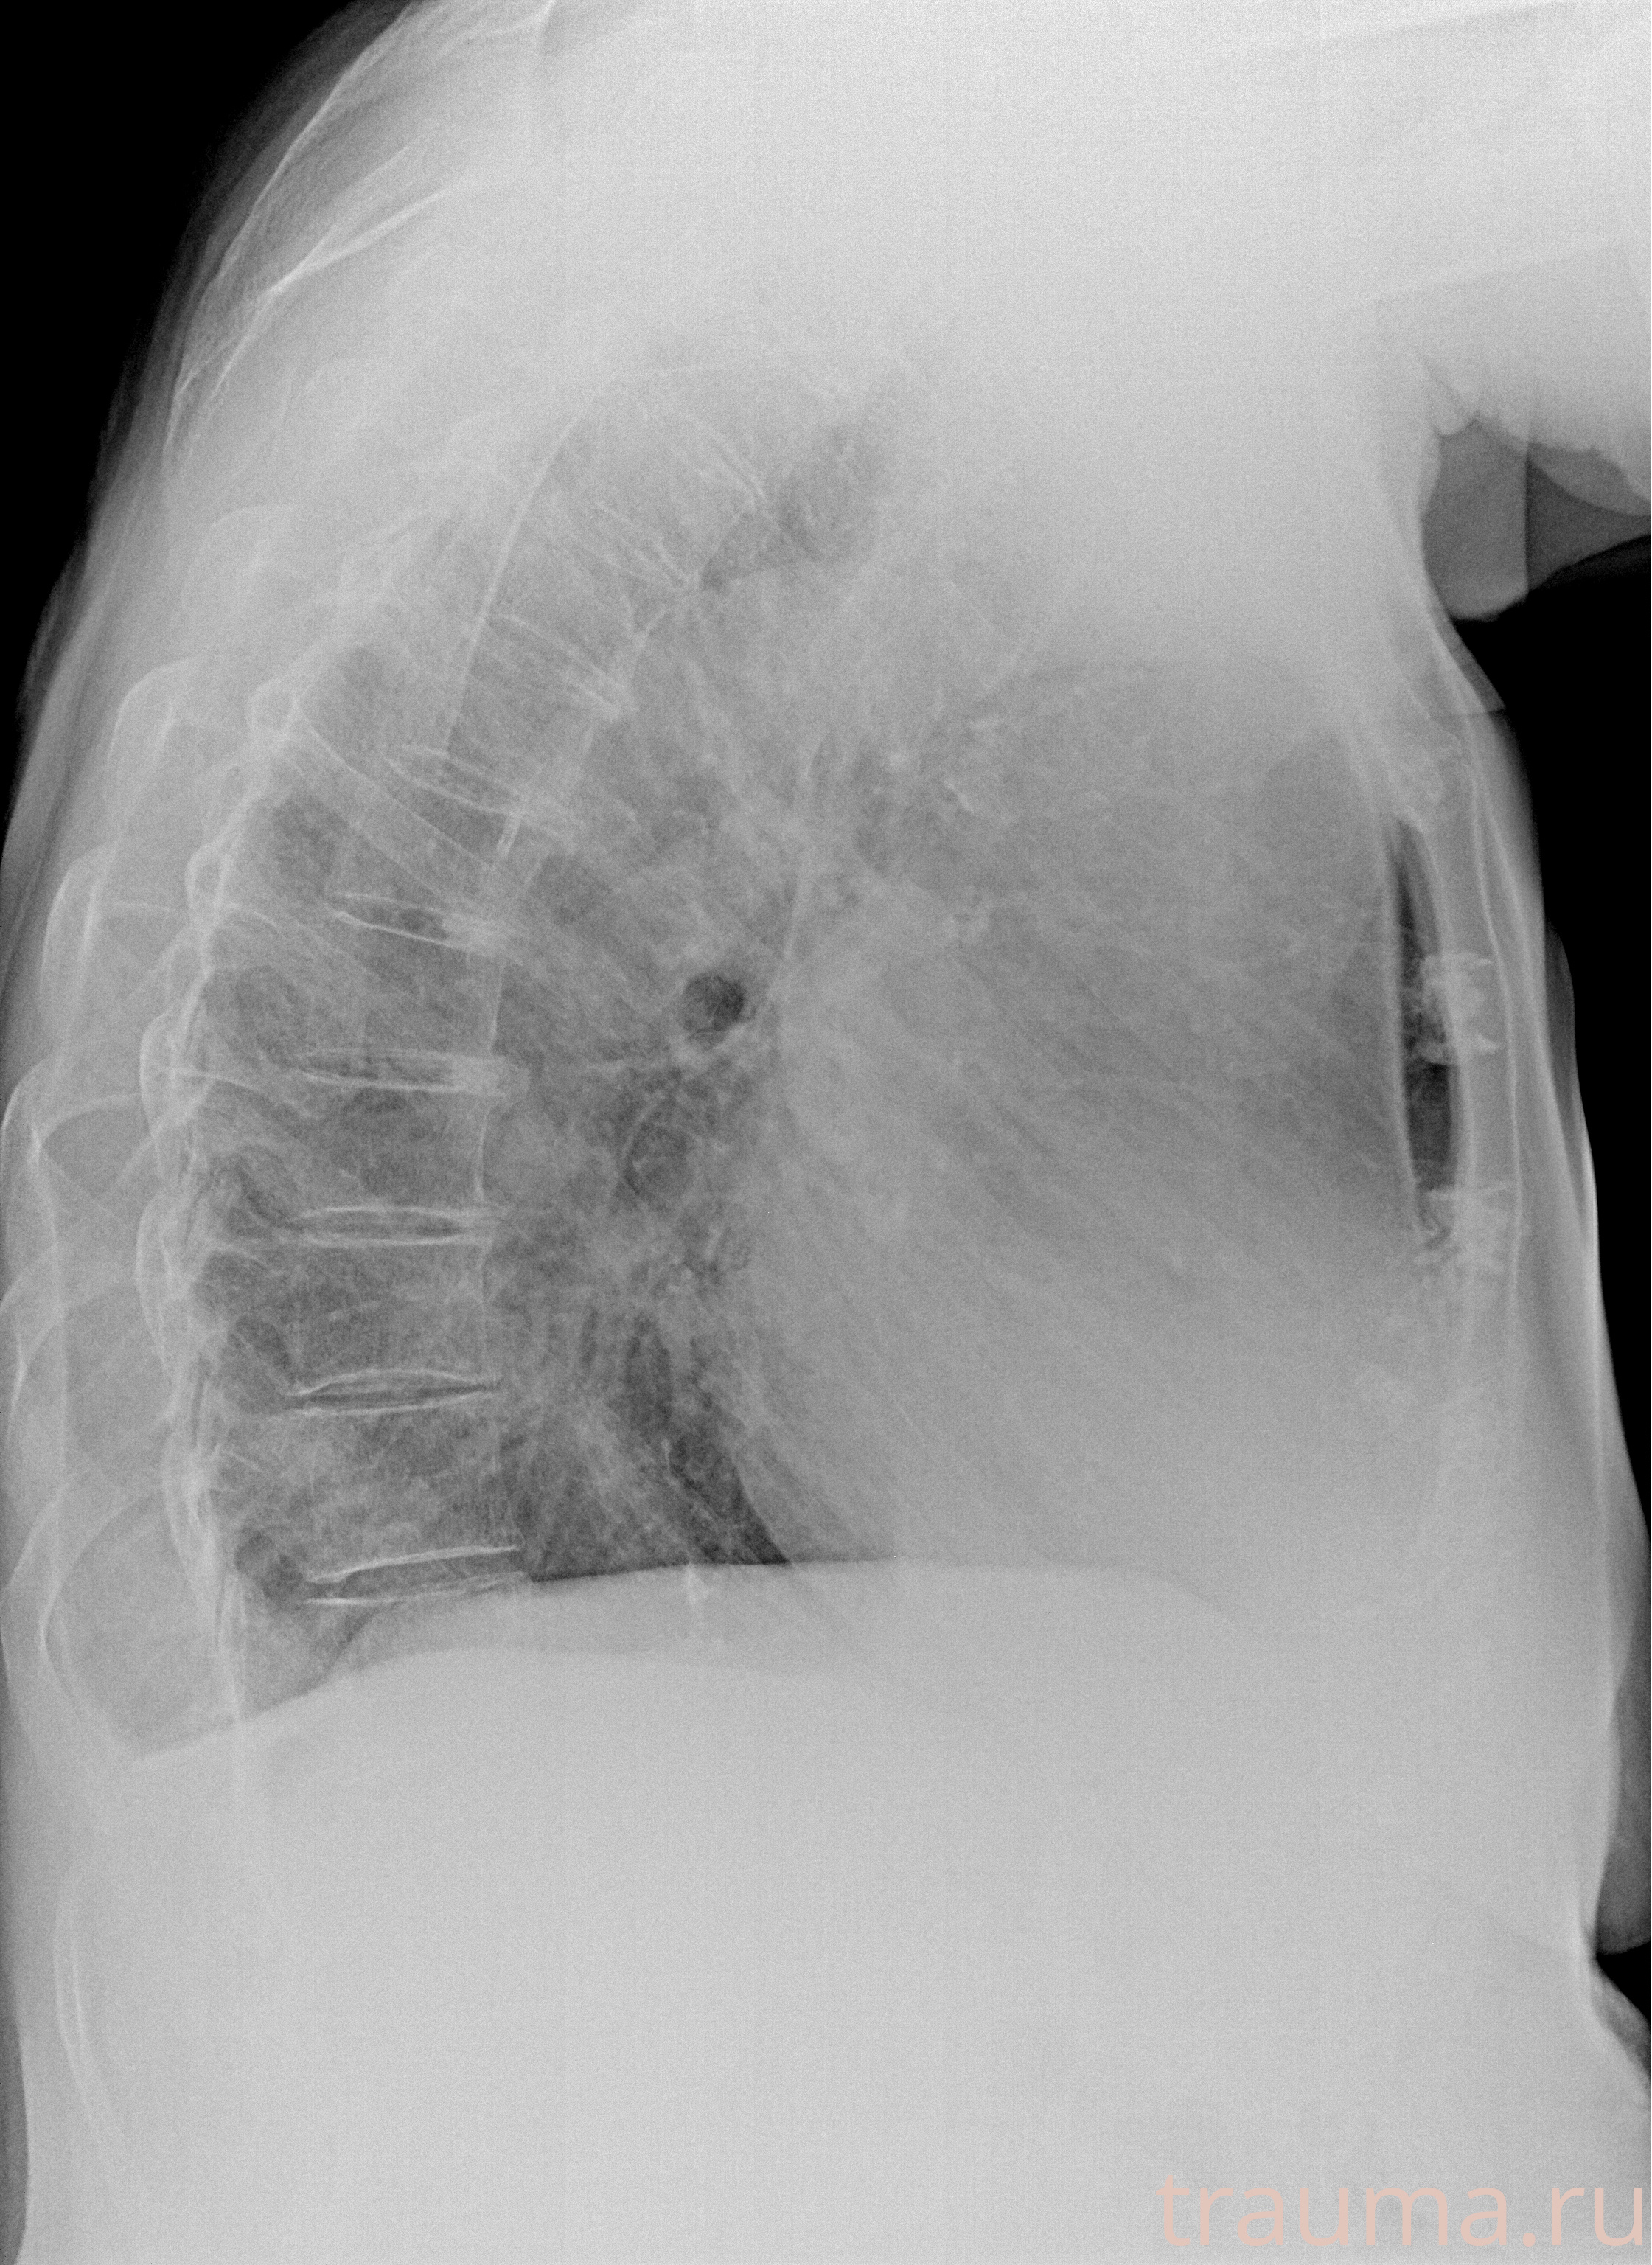

Рентгенограммы

Рентген на дому: по вашему адресу приезжает врач-рентгенолог, травматолог-ортопед с мобильным рентгеновским аппаратом, проводит диагностику травмы или заболевания, делает необходимые рентгенограммы, дает рекомендации по дальнейшему лечению. Получить качественные снимки в домашних условиях возможно благодаря уникальной методике, разработанной МосРентген Центром для института  Склифосовского

при переломе шейки бедра и пневмонии от компании МосРентген Центр - партнера Института имени Склифосовского